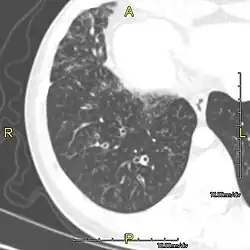

Around 80% of people with primary ciliary dyskinesia experience respiratory problems beginning within a day of birth. Many have a collapsed lobe of the lung and blood oxygen low enough to require treatment with supplemental oxygen.[1] Within the first few months of life, most develop a chronic mucus-producing cough and runny nose.[1] The main consequence of impaired ciliary function is reduced or absent mucus clearance from the lungs, and susceptibility to chronic recurrent respiratory infections, including sinusitis, bronchitis, pneumonia, and otitis media. Progressive damage to the respiratory system is common, including progressive bronchiectasis beginning in early childhood, and sinus disease (sometimes becoming severe in adults). However, diagnosis is often missed early in life despite the characteristic signs and symptoms.[2] In males, immotility of sperm can lead to infertility, although conception remains possible through the use of in vitro fertilization, there also are reported cases where sperm were able to move.[8] Trials have also shown that there is a marked reduction in fertility in females with Kartagener's syndrome due to dysfunction of the oviductal cilia.[9]

Many affected individuals experience hearing loss and show symptoms of otitis media which demonstrates variable responsiveness to the insertion of myringotomy tubes or grommets. Some patients have a poor sense of smell, which is believed to accompany high mucus production in the sinuses (although others report normal – or even acute – sensitivity to smell and taste). Clinical progression of the disease is variable, with lung transplantation required in severe cases. Susceptibility to infections can be drastically reduced by an early diagnosis. Treatment with various chest physiotherapy techniques has been observed to reduce the incidence of lung infection and to slow the progression of bronchiectasis dramatically. Aggressive treatment of sinus disease beginning at an early age is believed to slow long-term sinus damage (although this has not yet been adequately documented). Aggressive measures to enhance clearance of mucus, prevent respiratory infections, and treat bacterial superinfections have been observed to slow lung-disease progression. The predicted incidence is 1 in approximately 7500.[10]